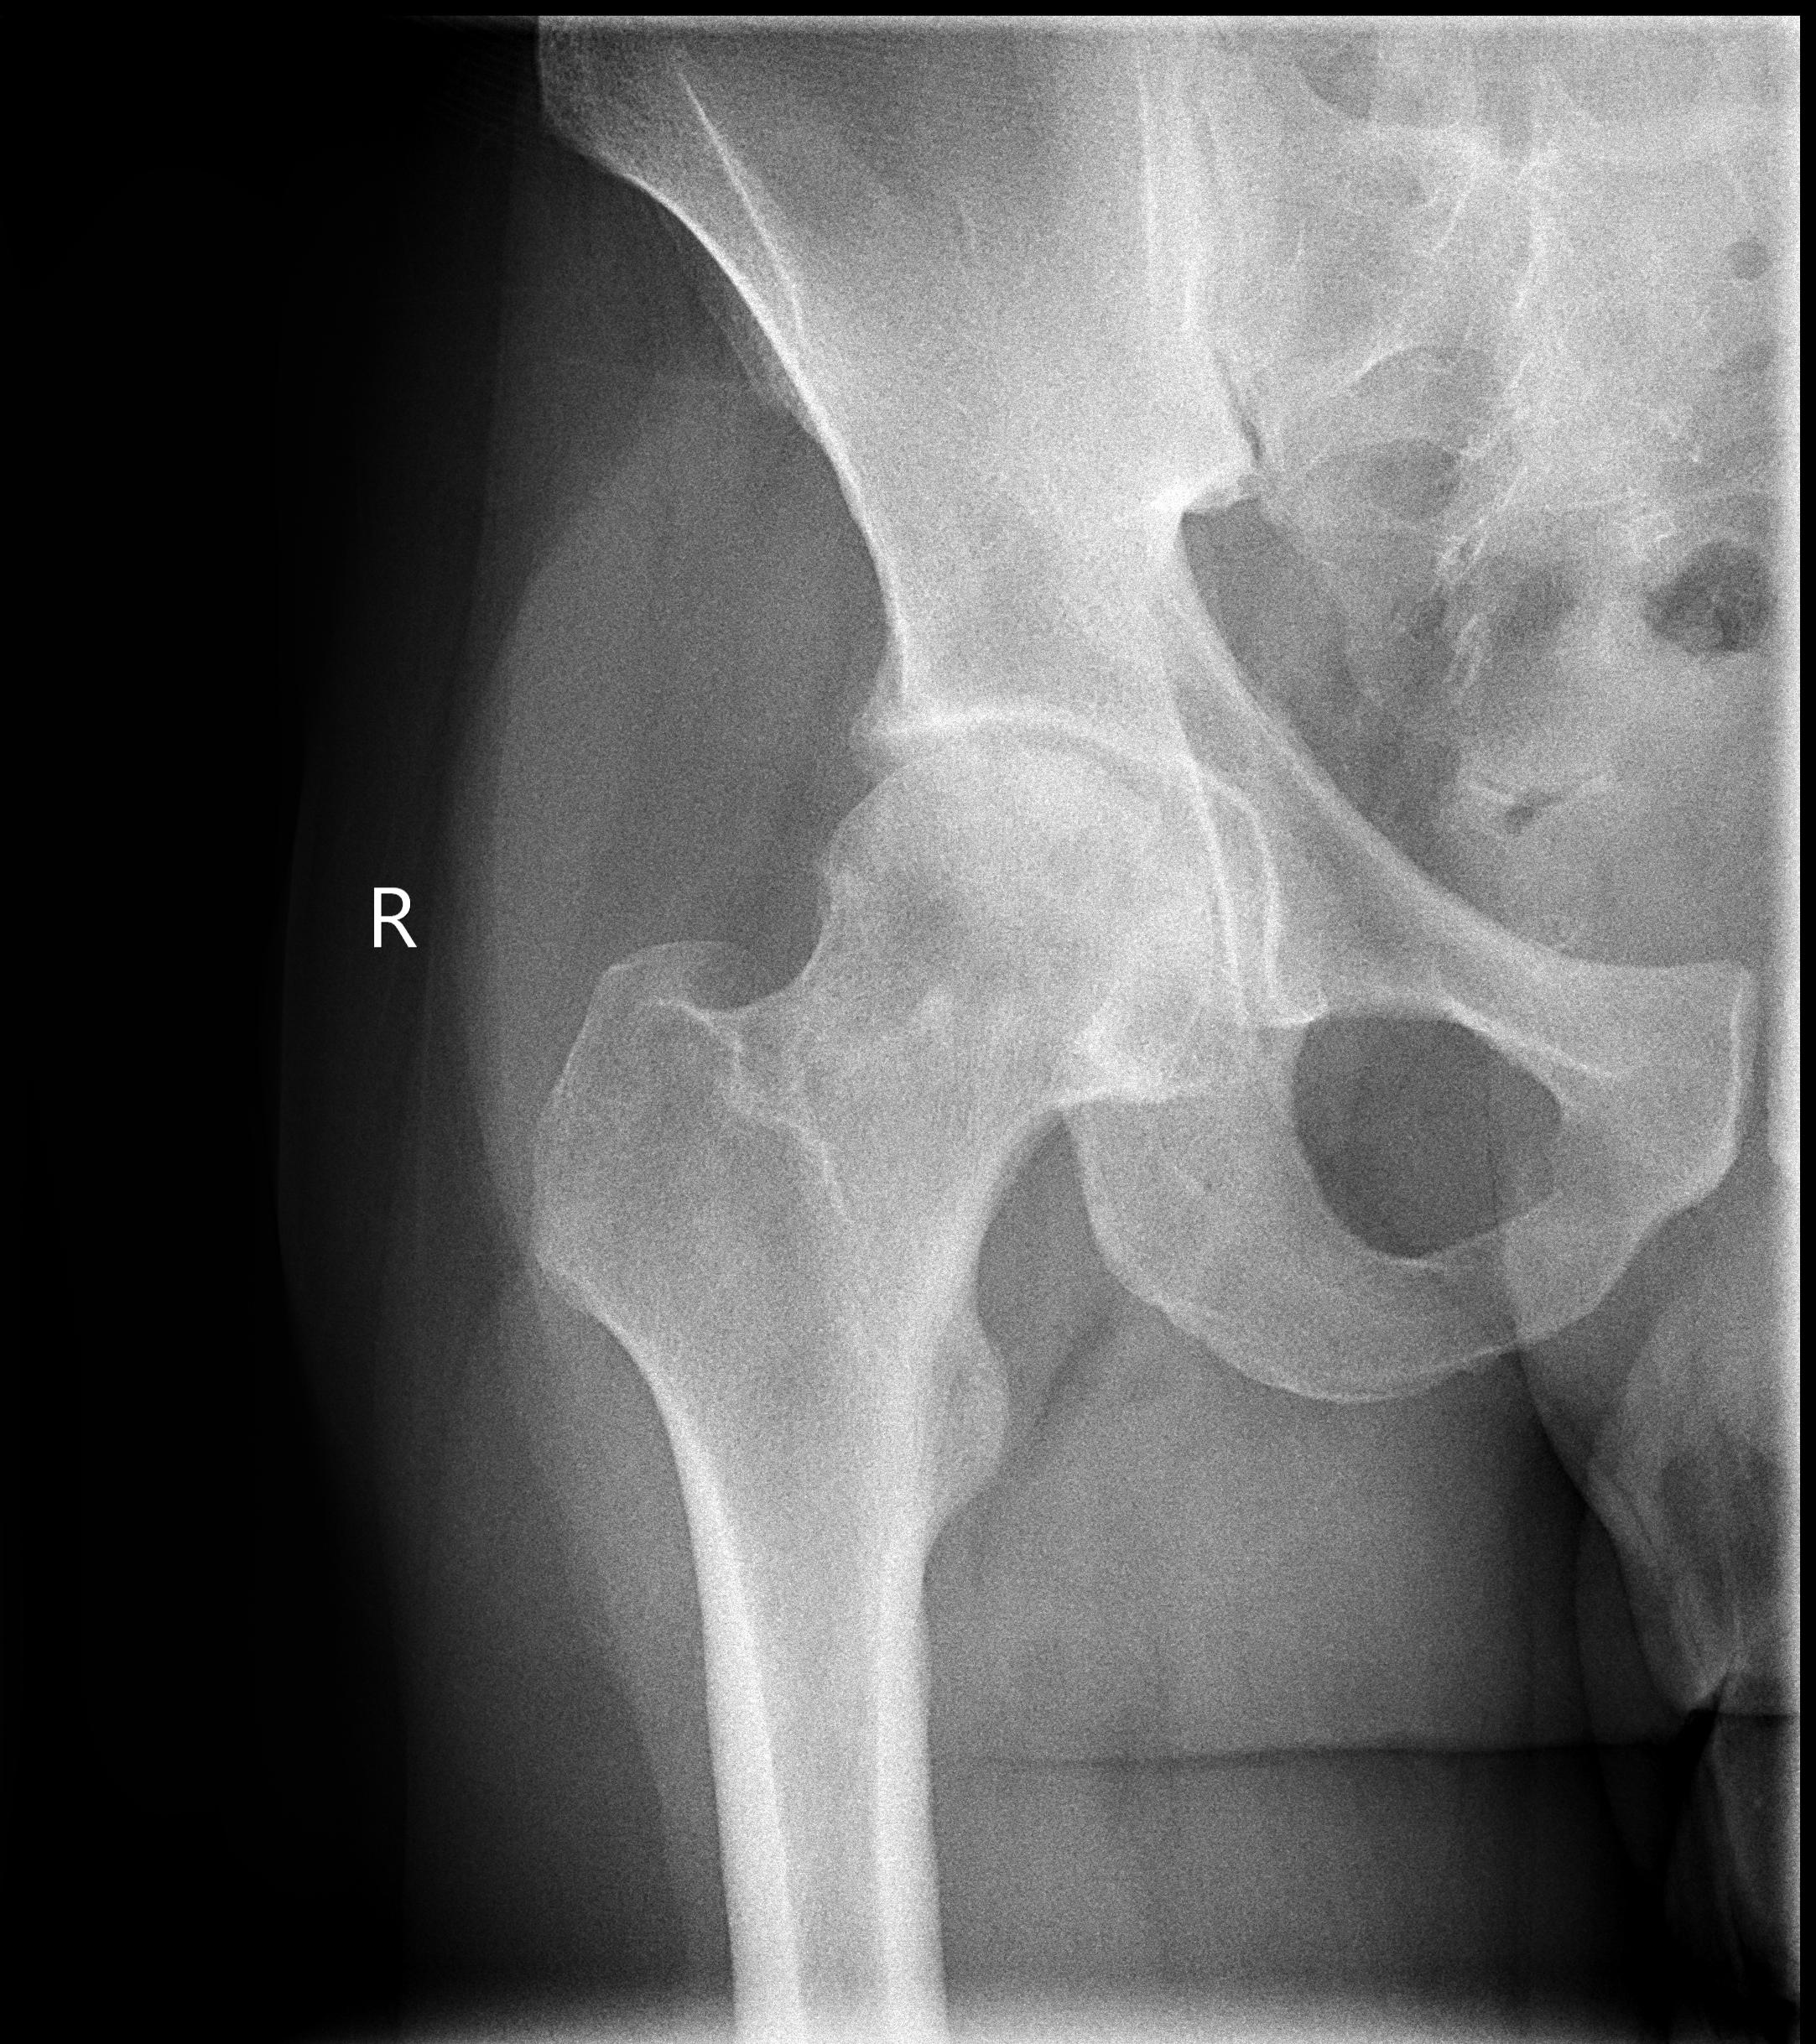

Для своевременного выявления ранних проявлений коксартроза нами применяется комплексный подход в диагностике данной патологии, включающий: опрос, осмотр сустава, проверка объема движения в нем, рентгенографию, компьютерную томографию (КТ), магнитно-резонансную томографию (МРТ) и ультразвуковое исследование (УЗИ) тазобедренного сустава.

На рентгенограммах тазобедренный сустав сохраняет нормальную форму, суставная щель умеренно или неравномерно сужена с субхондральным склерозированием костных суставных поверхностей, непостоянными краевыми костными разрастаниями (I стадия).

Рентгенологически суставная щель может быть равномерно или неравномерно сужена, ацетабулярная суставная впадина уплощена, присутствуют явления субхондрального склероза, краевые костные разрастания. Конфигурация головки бедренной кости, как правило, не нарушена (II стадия).

В подавляющем большинстве случаев диагноз коксартроза ставится при рентгенографии, где видны изменения формы и структуры костей, составляющих тазобедренный сустав. Однако рентгенографически в ряде случаев затруднительно зафиксировать ранние проявления артроза, так как хрящевая ткань суставных поверхностей на рентгеновских снимках не отображается и мы можем судить о дегенеративном процессе, когда он достаточно выражен, вызывая изменения ширины просвета рентгеновской суставной щели.

КТ тазобедренного сустава проведено с 2002 года в 80, МРТ с 2011 года — в 22 случаях. Предпочтение следует отдать МРТ, так как при данном виде исследования можно четко визуализировать суставную капсулу и связки, идентифицировать даже поверхностные изменения хрящевого слоя, а также мелкие очаги субкортикального трабекулярного отека губчатого вещества костной ткани. КТ позволяет оценить минимальные изменения структуры и формы костной ткани, однако в общем объеме получаемой информации уступая МРТ в информативности. При углубленном обследовании для уточнения диагноза «коксартроз» и степени его выраженности можно рекомендовать проведение именно МРТ тазобедренных суставов.

На ранних стадиях диагностировать артроз можно только при проведении КТ или МРТ.

Выводы. Таким образом, учитывая доступность и экономическую целесообразность, скрининговыми методами диагностики коксартроза являются рентгенография и УЗИ тазобедренных суставов. При несоответствии клинической картины и данных методов исследования необходимо КТ и (или) МРТ, что позволяет повысить качество диагностики и назначить адекватную терапию.